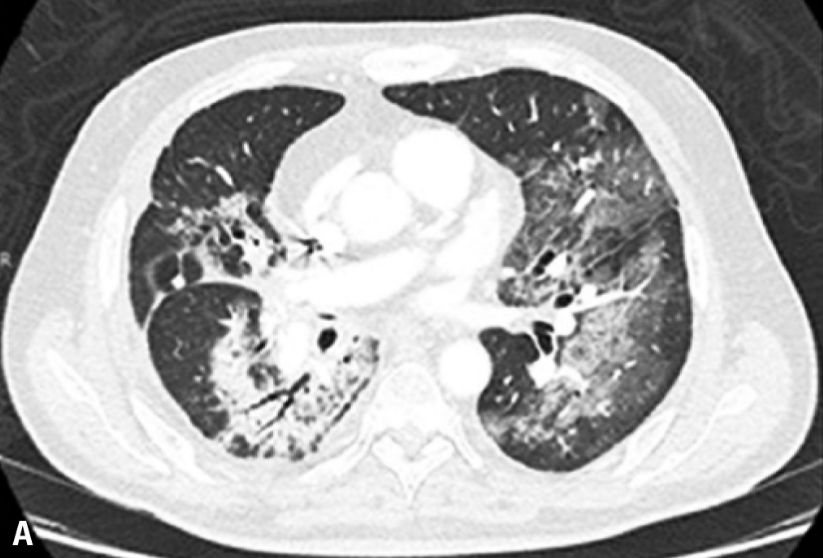

患者是一名81岁的老年男性,身患ⅢA期难治性肺腺癌。病人在进行手术治疗后又接受了放疗和卡铂+培美曲塞的辅助化疗。在随访4个月后,病人的病情出现了局部复发,在放疗治疗无效后,病人又接受了卡铂和紫杉醇的姑息性化疗,但是其病情并未得到有效的控制。同样,病人在传统治疗无效后选择了帕博利珠单抗每3周2mg/kg的免疫治疗方案。在治疗4个疗程后,病人开始出现呼吸困难和干咳,血氧饱和度也降至80%。CT检查显示双侧肺部出现弥漫性浸润灶,血常规检查显示其白细胞计数增高。所幸的是,病人在对症使用甲基强的松龙2mg/kg和抗生素治疗后,其肺部炎症得到了比较好的控制。

在本次报道的5名病人中,仅有一人为5级不良反应,并最终去世。其他4名病人均为3级不良反应,在接受糖皮质激素治疗后病情都有改善。大多数病人的CT表现肺部的磨玻璃样改变,早期临床表现为咳嗽和呼吸困难,不论对于病人还是医务工作者来说,免疫性肺炎的早诊断和早治疗都尤为重要,以上报道的病人中,有几人就是因为早诊断早治疗,在很短的时间内肺炎症状就得到了快速的缓解,因此我们说:肺炎不可怕,“早”字是关键。